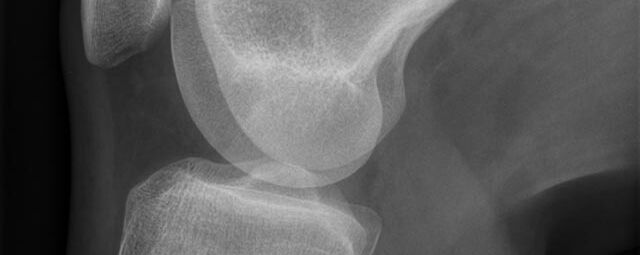

Konventionelles Röntgen

Der Begriff Röntgen, oder auch Röntgendiagnostik bezeichnet ein Verfahren in der Radiologie, bei dem von einer Röntgenröhre elektromagnetische Wellen (Röntgenstrahlen) durch die zu untersuchende Körperregion des Patienten gesendet werden. Je nach Dichte der Gewebeart des Körpers (z.B. Knochen oder Lunge) werden die Röntgenstrahlen im Körper unterschiedlich stark abgeschwächt. Ein digitaler Detektor empfängt dann die Röntgenstrahlen, die in abgeschwächter Form den Körper wieder verlassen haben. Daraus wird das Röntgenbild erzeugt.

Die zu untersuchenden Anteile des Körpers werden meistens

in 2 unterschiedlichen Projektionsebenen dargestellt.